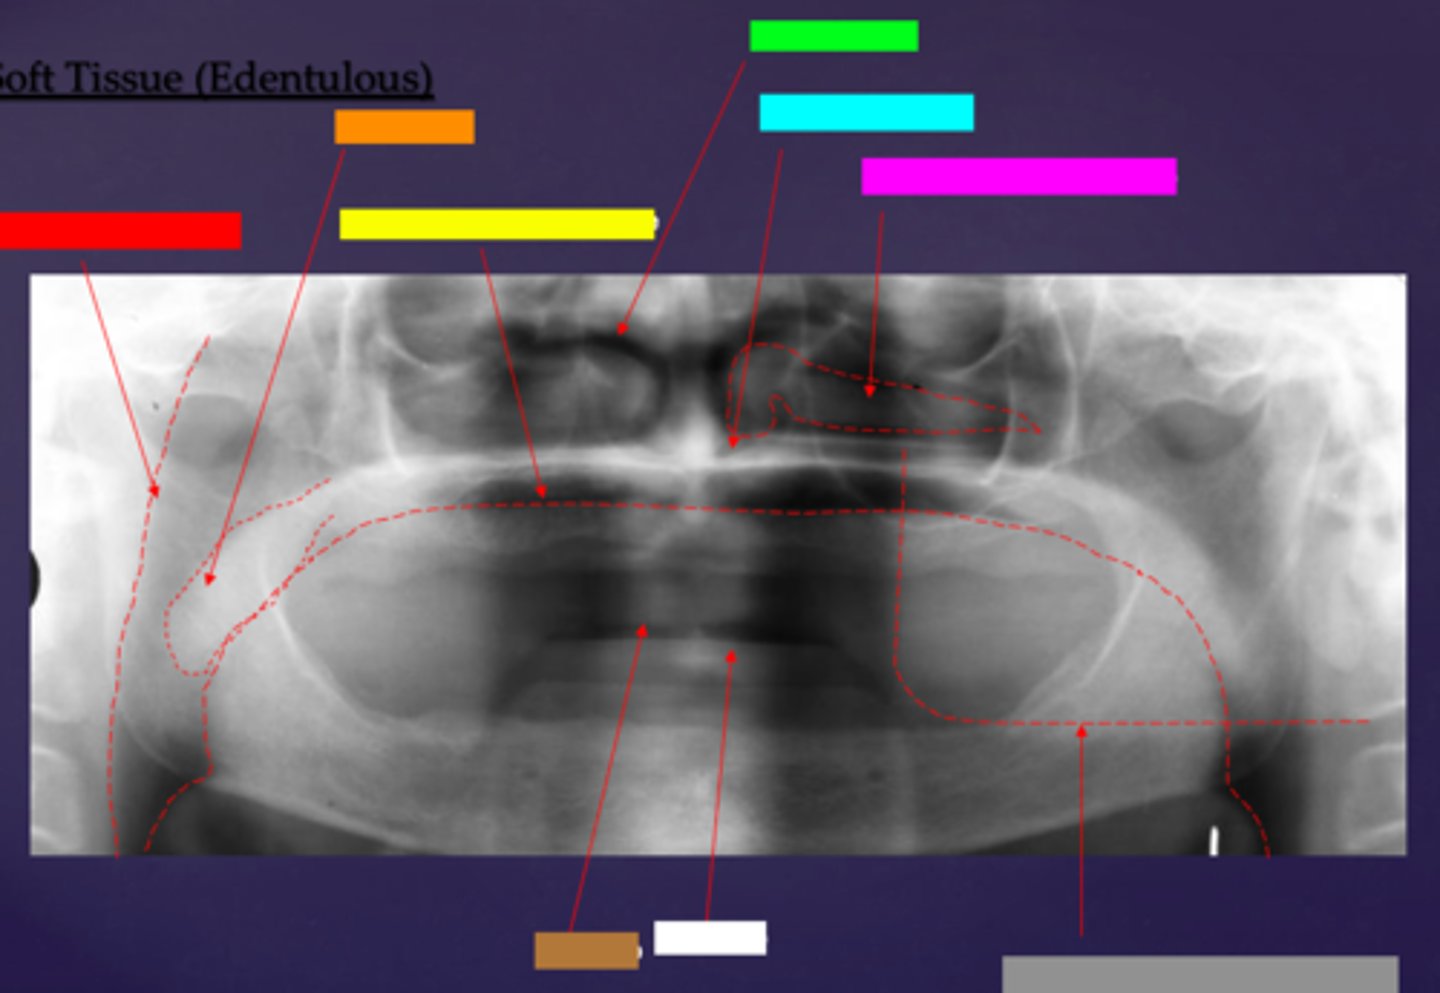

ID the soft tissue anatomy indicated by the arrow pointing from the red box:

posterior pharyngeal wall

ID the soft tissue anatomy indicated by the arrow pointing from the orange box:

soft palate

ID the soft tissue anatomy indicated by the arrow pointing from the yellow box:

dorsal surface of tongue

ID the soft tissue anatomy indicated by the arrow pointing from the green box:

middle nasal meatus

ID the soft tissue anatomy indicated by the arrow pointing from the light blue box:

inferior nasal meatus

ID the soft tissue anatomy indicated by the arrow pointing from the hot pink box:

inferior nasal concha (turbinate)

ID the soft tissue anatomy indicated by the arrow pointing from the brown box:

upper lip

ID the soft tissue anatomy indicated by the arrow pointing from the white box:

lower lip

ID the soft tissue anatomy indicated by the arrow pointing from the grey box:

ghost image of opposite mandible

ala of nose

nasal septum

columna (the septum separating the nostrils)

tragus

ear lobe